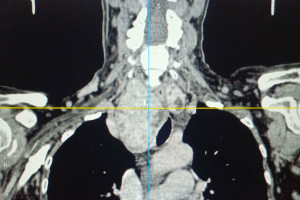

Особую сложность представляло анатомическое расположение зоба. По словам хирурга, расположение зоба было частично загрудинным, образование опускалось за грудину примерно на две трети. А правая доля щитовидной железы подходила вплотную к плечеголовному стволу — крупному артериальному сосуду. Кроме того, зоб циркулярно охватывал трахею, сдавливая ее со всех сторон и вызывая у пациентки затруднение дыхания даже при небольшой физической нагрузке.

Операции предшествовало комплексное обследование, включавшее компьютерную и магнитно-резонансную томографию, в результате которых было принято решение о проведении срочного хирургического вмешательства. В настоящий момент состояние пациентки стабилизировалось, она чувствует себя хорошо выписана домой для дальнейшей реабилитации.